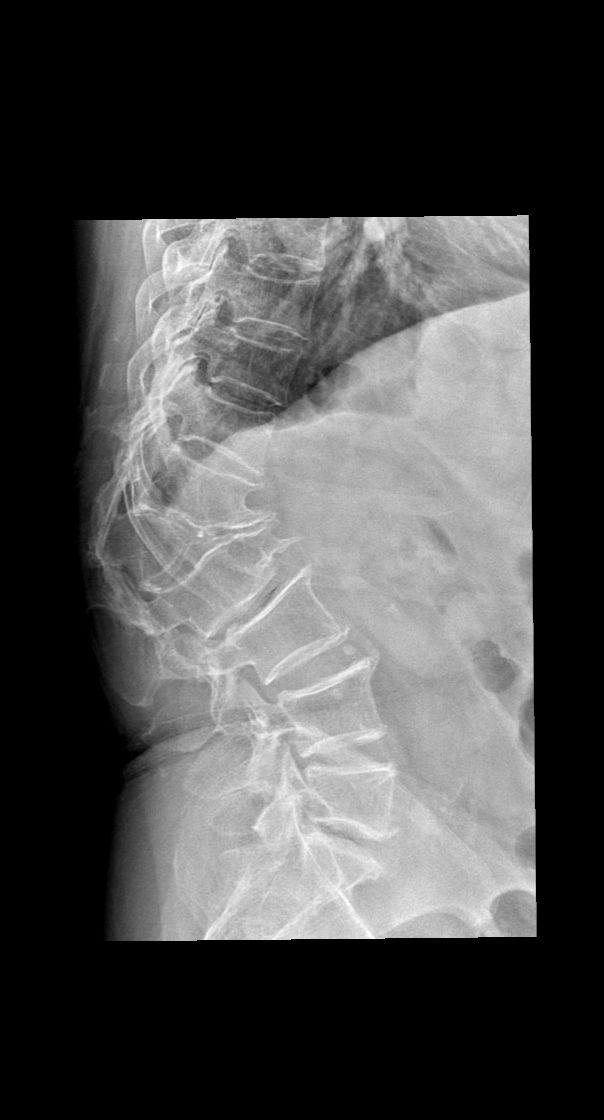

男,79y,腰疼就诊